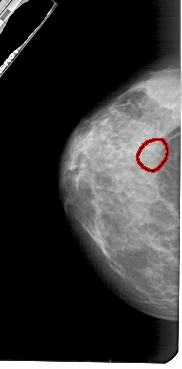

A_1888_1.LEFT_CC

LEFT_CC LINES 5161 PIXELS_PER_LINE 2536 BITS_PER_PIXEL 12 RESOLUTION 43.5 OVERLAY

FILE: A_1888_1.LEFT_CC.OVERLAY

TOTAL_ABNORMALITIES 1

ABNORMALITY 1

LESION_TYPE CALCIFICATION TYPE PUNCTATE DISTRIBUTION CLUSTERED

ASSESSMENT 4

SUBTLETY 2

PATHOLOGY BENIGN

TOTAL_OUTLINES 1

BOUNDARY